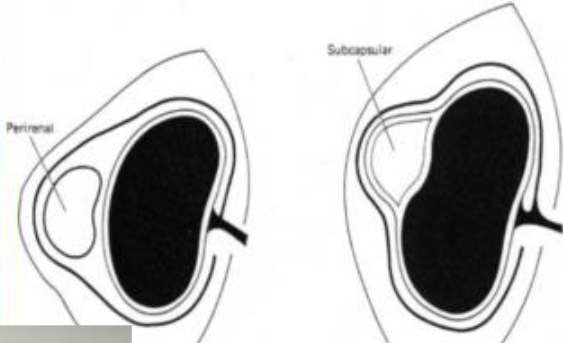

2 types of cystic disease placement

A

perirenal

subcapsular